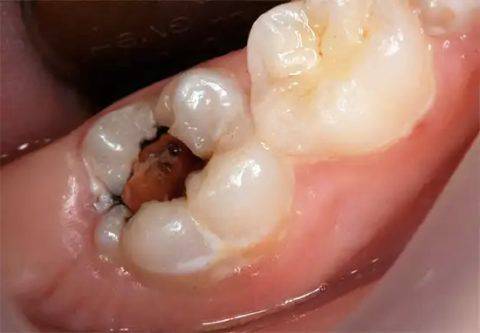

Переход кариеса в пульпит происходит примерно так: в зубе образуется небольшая

кариозная полость. Если лечения нет, то

кариес продолжает разрушение зуба и

достигает своей завершающей стадии –

глубокого кариеса . При котором между

полостью и нервом остается тончайшая стеночка. Нерв при этом еще не поврежден,

хотя и реагирует уже не совсем адекватно. Если кариес не пролечен, то нерв

возмущается такой халатностью своего владельца и вовлекается в воспаление. Так

кариес перерастает в пульпит .

Если ничего не предпринимать, кариозное поражение будет приобретать все большие размеры, пока до нерва не останется лишь тонкая стенка. Когда же разрушится и она, процесс перейдет в стадию пульпита. А это уже совсем другое состояние: очень болезненное и требующее сложного лечения, поскольку поражается самая чувствительная часть зуба. Очень часто у пациента с таким диагнозом удаляют нерв.